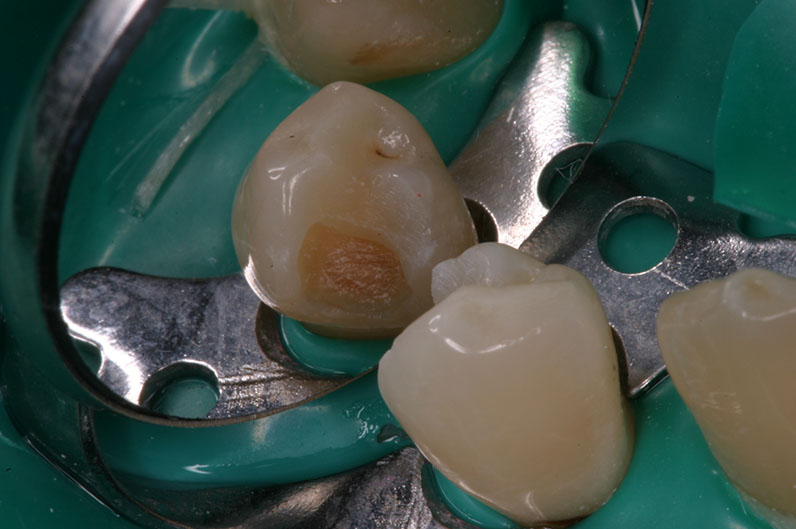

Facelight stanowi istotną pomoc kliniczną przy wykrywanie ognisk próchnicy twardych tkanek zęba, a w szczególności zainfekowanej zębiny. Istnieją znacznie lepsze możliwości wykrywania i tym samym doszczętnego usuwania próchnicowo zmienionych tkanek niż za pomocą metod tradycyjnych (zgłębnik czy wybarwianie). Metody tradycyjne nie pozwalają w sposób bezpośredni i pewny określić ilości i lokalizacji próchnicowo zmienionej zębiny. Natomiast sonda świetlna Facelight wraz z okularami diagnostycznymi stanowią narzędzie pozwalające na bezpośredni podgląd i bardzo dokładne usunięcie pozostałości próchnicy w ubytku.

Konstrukcja sondy świetlnej Facelight bazuje na tak zwanej technice FACE (Fluorescence Aided Caries Excavation) skuteczność tej techniki została potwierdzona wieloma badaniami naukowymi.